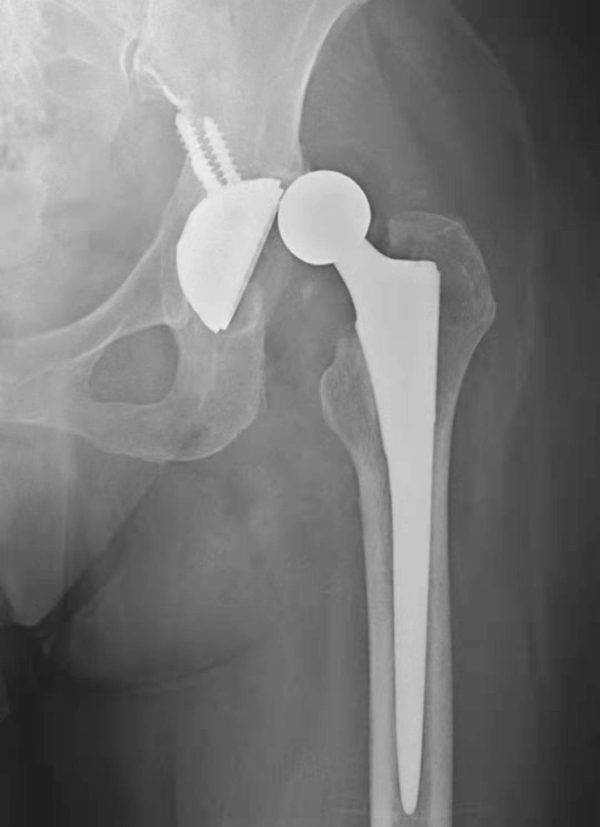

图2 无菌性松动

平片,示右侧股骨上段骨质疏松,人工股骨柄周围明显骨质吸收,透亮带明显增宽,髋臼杯位置未见改变